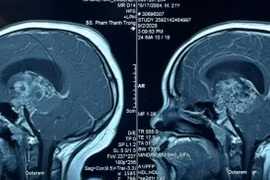

Phẫu thuật khẩn cấp cứu chàng trai 21 tuổi hôn mê sâu do u sọ hầu tái phát

U sọ hầu là loại u não hiếm gặp tuy lành tính nhưng đặc biệt nguy hiểm vì gần vị trí vùng tuyến yên và vùng trên yên.